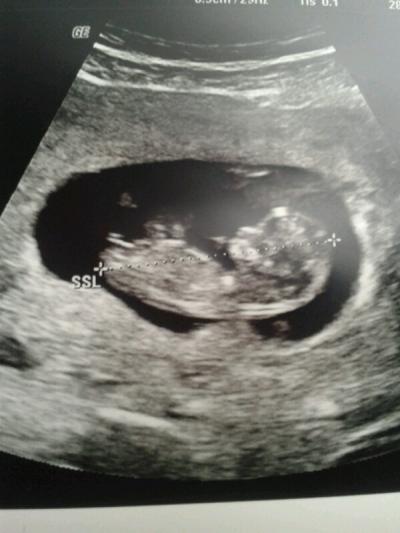

Hi Mädels, bei meinen letzten Termin hat meine Ärztin irgendwie direkt auf das Geschlecht gezoomt und meinte das Geschlecht sei auch schon ausgebildet, weiterhin sagte sie da sei ein Zipfel, ein Mädchen könne aber noch nicht ausgeschlossen werden. Ich hatte sie zuvor gar nicht gefragt und war daher irgendwie etwas überrascht darüber, dass sie überhaupt dahin gezoomt hat. Ich habe überhaupt nicht auf diese Aussage reagiert und danach dachte ich aber ständig dran, ob sie mir vielleicht damit einen Wink mit Tendenz zum Jungen geben wollte. Einen bestimmten Wunsch habe ich ehrlich gesagt nicht. Gespannt bin ich dennoch. Der Kinderwunsch ist soo groß, dass ich es kaum erwarten kann mein Baby, mein Wunder endlich im Arm zu halten. Bis zum nächsten Termin gucke ich mir immer öfter das Bild an und ich frage mich, ob da irgendwie tatsächlich dieser "Zipfel" zu erkennen ist und ob es das eine offensichtliche da ist, kann es das sein oder ist es die Nabelschnur? Kennt sich da jemand gut aus oder hat ein ähnliches Bild? Möchte nicht ständig negativ denken und die ständige Angst, dass noch was schief läuft ausblenden, deswegen lenke ich meine Gedanken lieber in Richtung "Outing" etc. :-) Hoffe ihr habt Verständnis und Lust mit zu raten. Bin bislang nur im Mai Forum aktiv gewesen. Stand derzeit: 11+6 ssw. LG und danke.

Bild zu Sieht man in diesem Profil etwas vom Geschlecht? - Schwanger - wer noch? Rund um die Schwangerschaft

Das was man da sieht kann unmöglich der Zipfelchen sein, denn dann hätte es zur Geburt wohl eher einen Riesenzipfel... nö... da kann man nix sehen und ich halte das auch noch für zu früh zu spekulieren

Kann gut sein, dass es sich hier um die Geschlechtsknospe handelt. Schaut am Anfang bei Mädels und Jungs fast gleich aus. Mädels haben zu diesem Zeitpunkt noch eine relativ große Klitoris. Das verwächst sich erst später. Gute Ultraschaller könnwn aber schon so früh anhand des Winkels etc eine Tendenz sagen

Hi, Habe neulich Bilder gesehen. Der Winkel deutet auf Mädchen hin. Aber ich bin kein Frauenarzt. Bin ja gespannt, was raus kommt. Liebe Grüße Nicole

Ich habe vor... 2-3 Tagen die gleiche Frage hier gestellt. Habe mich danach auch noch sonst wo umfragt. Das Result ist Folgendes: Beide Geschlechter haben diesen Zipfel und es je nach dem in welchem Winkel der zurm Körper absteht, kann man tatsächlich bestimmen ob Mädchen oder Junge. Allerdings liegen bei der 12. Ssw, in Welche du ja mit 11+6 noch so gerade reinpasst, die richtigen Schätzungen bei nur zu 50%. Das liegt daran dass der Zipfel noch im Winkel steigen kann. Jungs würden also falsch als Mädchen gedeutet. Etwas recht Zuverlässiges, mit 90% richtigen Outings in der Statistik, ist aber erst ab der 14. Ssw zu rechnen... Und natürlich muss die Person, die den Ultraschall macht, schon ein bisschen was davon verstehen.